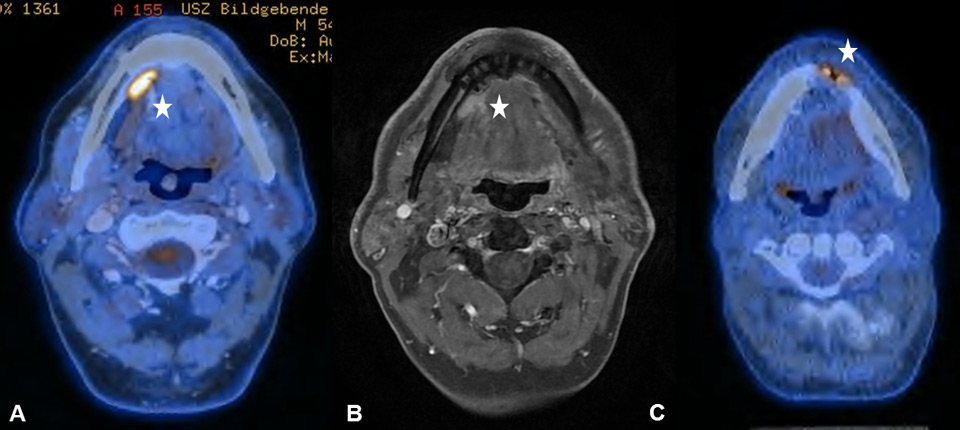

Figure 2

(A) Increased uptake in the right parotid gland in a 56-year old patient with a past medical history of radical parotidectomy and adjuvant radiation therapy (RT) on the left side due to a parotid gland carcinoma. Physiological uptake in the cervical brown fat tissue and the floor of mouth (FOM) muscles. (B) Increased uptake in the left paramedian FOM muscles due to muscular dysbalance in a 69-year old patient with a past medical history of surgical resection and RT of a right-sided base of the tongue carcinoma

It is known that PET-CT is more accurate in detecting HNC recurrence than conventional physical examinations alone and that therefore negative periodic clinical examinations may be complemented by FDG PET-CT [8, 15]. As expected, we observed PET-CT to be a well-established ruling-out test at the expense of a decreased positive predictive value and specificity [7–9]. However, interpretation of indistinct FDG-positive findings remains challenging because of a high number of false-positive lesions and the necessity for potentially unnecessary and invasive diagnostic investigations. As in previous studies, we found typical foci of increased FDG uptake [16, 17]. The pharyngeal mucosa frequently causes physiological FDG uptake, hence the interpretation is usually unproblematic as long as the uptake is located superficially along the mucosal plane in linear configuration [18]. The palatine tonsils and other lymphatic structures of the Waldeyer’s ring typically exhibit FDG uptake, which most likely reflects a so-called “physiological inflammation” of the lymphatic tissue due to confrontation with antigens [18, 19] (fig. 1A). Furthermore, muscles of mastication and intrinsic tongue muscles were shown to be highly sensitive to exogenous confounders such as chewing gum during examination and therefore a good quality of PET-CT/MRI clearly depends on the compliance of the patient [20, 21] (fig. 1B). With regard to the floor of mouth (FOM) muscles, a recent study investigating the effect of a supine versus a sitting position on physiological FDG accumulation, did not find any alterations and concluded that there is no trick to avoid or reduce this kind of disturbing FDG uptake [22]. The correlation between muscular activity and increased FDG uptake was also shown for the larynx, since talking can cause FDG uptake in the muscles of phonation as well as in the vocal cords [18, 23]. In terms of FDG uptake in the salivary glands, the parotid, submandibular and sublingual glands may all reveal mild to moderate symmetric or asymmetric uptake, although these findings underlie a marked inter-individual variability [16, 17]. As there is a close relationship between reduction in FDG uptake into the salivary glands and increasing doses of RT, we found five patients with asymmetric salivary gland FDG uptake due to surgical treatment and RT to the contralateral side [24] (fig. 2A). Similarly, we observed four patients with asymmetric FDG uptake in the tongue and FOM as a consequence of muscular imbalance due to contralateral surgical treatment (fig. 2B). Another well-known phenomenon is the increased FDG uptake in the contralateral vocal cord if a recurrent laryngeal nerve palsy is present (fig. 3AB).

Typical post-surgical findings were inflammatory FDG uptake of the tongue and the oral cavity due to transoral surgical resections or a shifted submandibular gland owing to a pectoralis major myocutaneous flap (fig. 5AB). Patients after laryngectomy, formation of a tracheostoma and insertion of voice prosthesis frequently showed increased FDG-activity around the voice prosthesis (fig. 6AB). Implantation of synthetic materials in the head and neck region, such as a voice prosthesis, can cause increased mucus production and tracheal wall damage with accompanying immunological cell accumulation and then increased FDG uptake [31]. Lastly, dental implants or non-removable bridgework can also cause artefacts in PET-CT [32]. However, as it was previously shown by our group, those artefacts might partly be reduced in PET-MRI [11, 33]. Therefore, PET-MRI seems to be an additional tool to complement PET-CT, especially when evaluating the oropharynx and oral cavity, since synthetic material typically causes artefacts in this region.